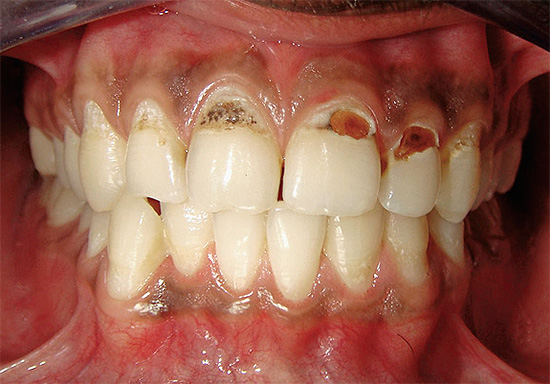

A foto a seguir mostra claramente a cárie profunda na região cervical: